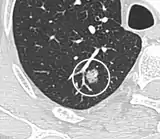

- In case of calcifications, a popcorn-like appearance indicates a hamartoma, which is benign.[3]